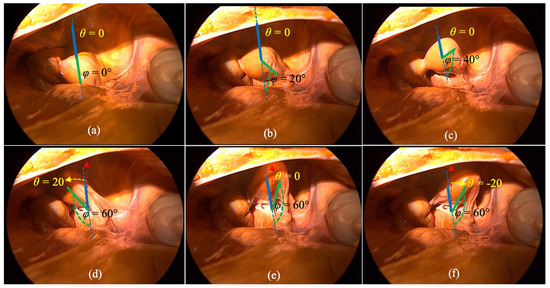

Figure 19 shows the laparoscopic views of the experiments conducted on a cadaver with the help of extra light through a medium-size incision in the abdomen. Figure 19a–c,e depict when the Roll angle ( θ ) = 0° with varied Pitch angles ( φ ) (0°, 20°, 40°, and 60°, respectively), while Figure 19d,f depicts when the motion Pitch angles ( φ ) = 60° but the Roll angles ( θ ) are 20° and −20°.

Figure 19. The results with extra external light during cadaver experiments; (ac,e) showing when the Roll angle ( θ ) = 0° with varied Pitch angles ( φ ) (0°, 20°, 40°, and 60°, respectively), while (d,f) showing when the motion Pitch angles ( φ ) = 60° but the Roll angles ( θ ) are 20° and −20°.